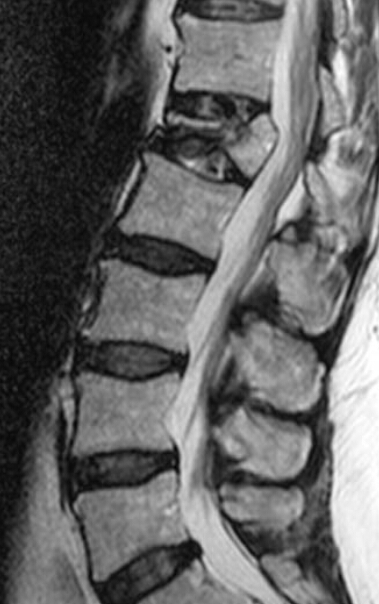

The patient is 70 years old. What is the dianosis? What are the radiographic features you see?

osteoporosis

radiographic features: cortical thinning, resorption of nonstress-bearing trabeculae, accentuated vertical struts, altered vertical shape (codfish deformity), schmorl’s nodes, endplate infractions